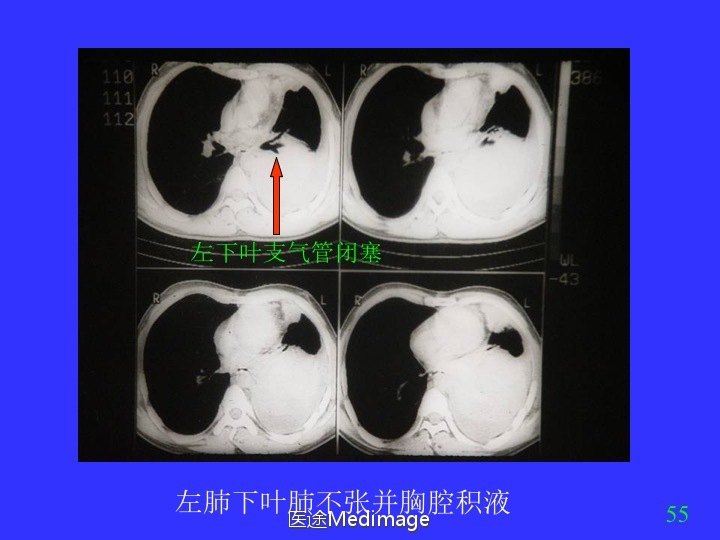

胸部CT阅读与诊断(三)各种肺不张